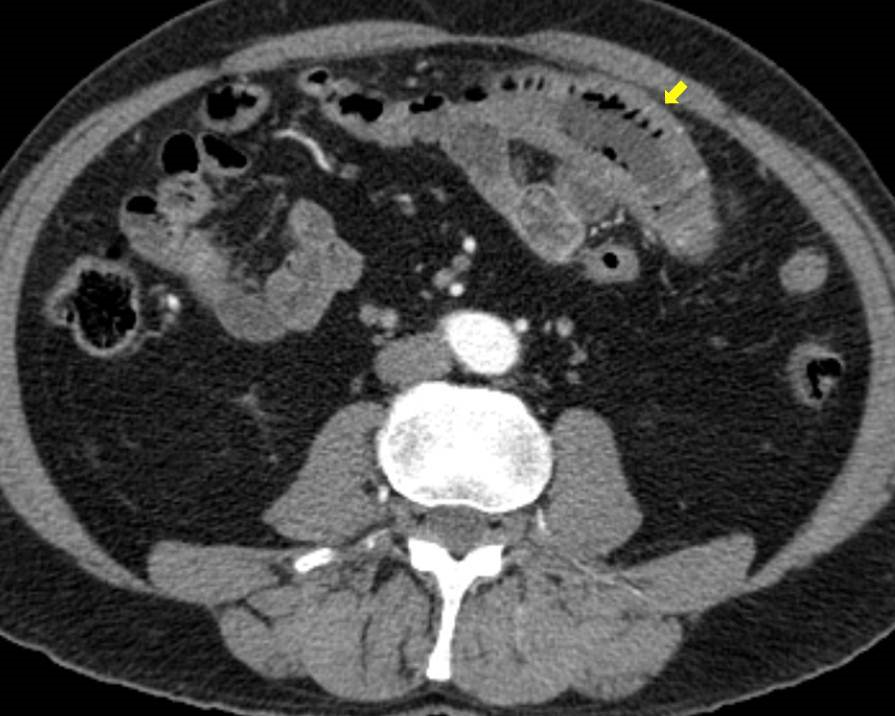

Acute abdominal pain is one of the most common conditions encountered in the emergency department. The differential diagnosis of acute abdominal pain is extensive and identifying the underlying etiology can be challenging. We report a case of acute transient ischemic jejunitis due to symptomatic isolated superior mesenteric artery dissection in a patient with no cardiovascular risk factors or autoimmune diseases. Symptomatic isolated superior mesenteric artery dissection is a rare cause of acute abdominal pain usually treated in the surgical department. The patient had criteria for conservative treatment and rapidly recovered. We highlight a rare condition which should be taken into account for the differential diagnosis of acute abdominal pain.